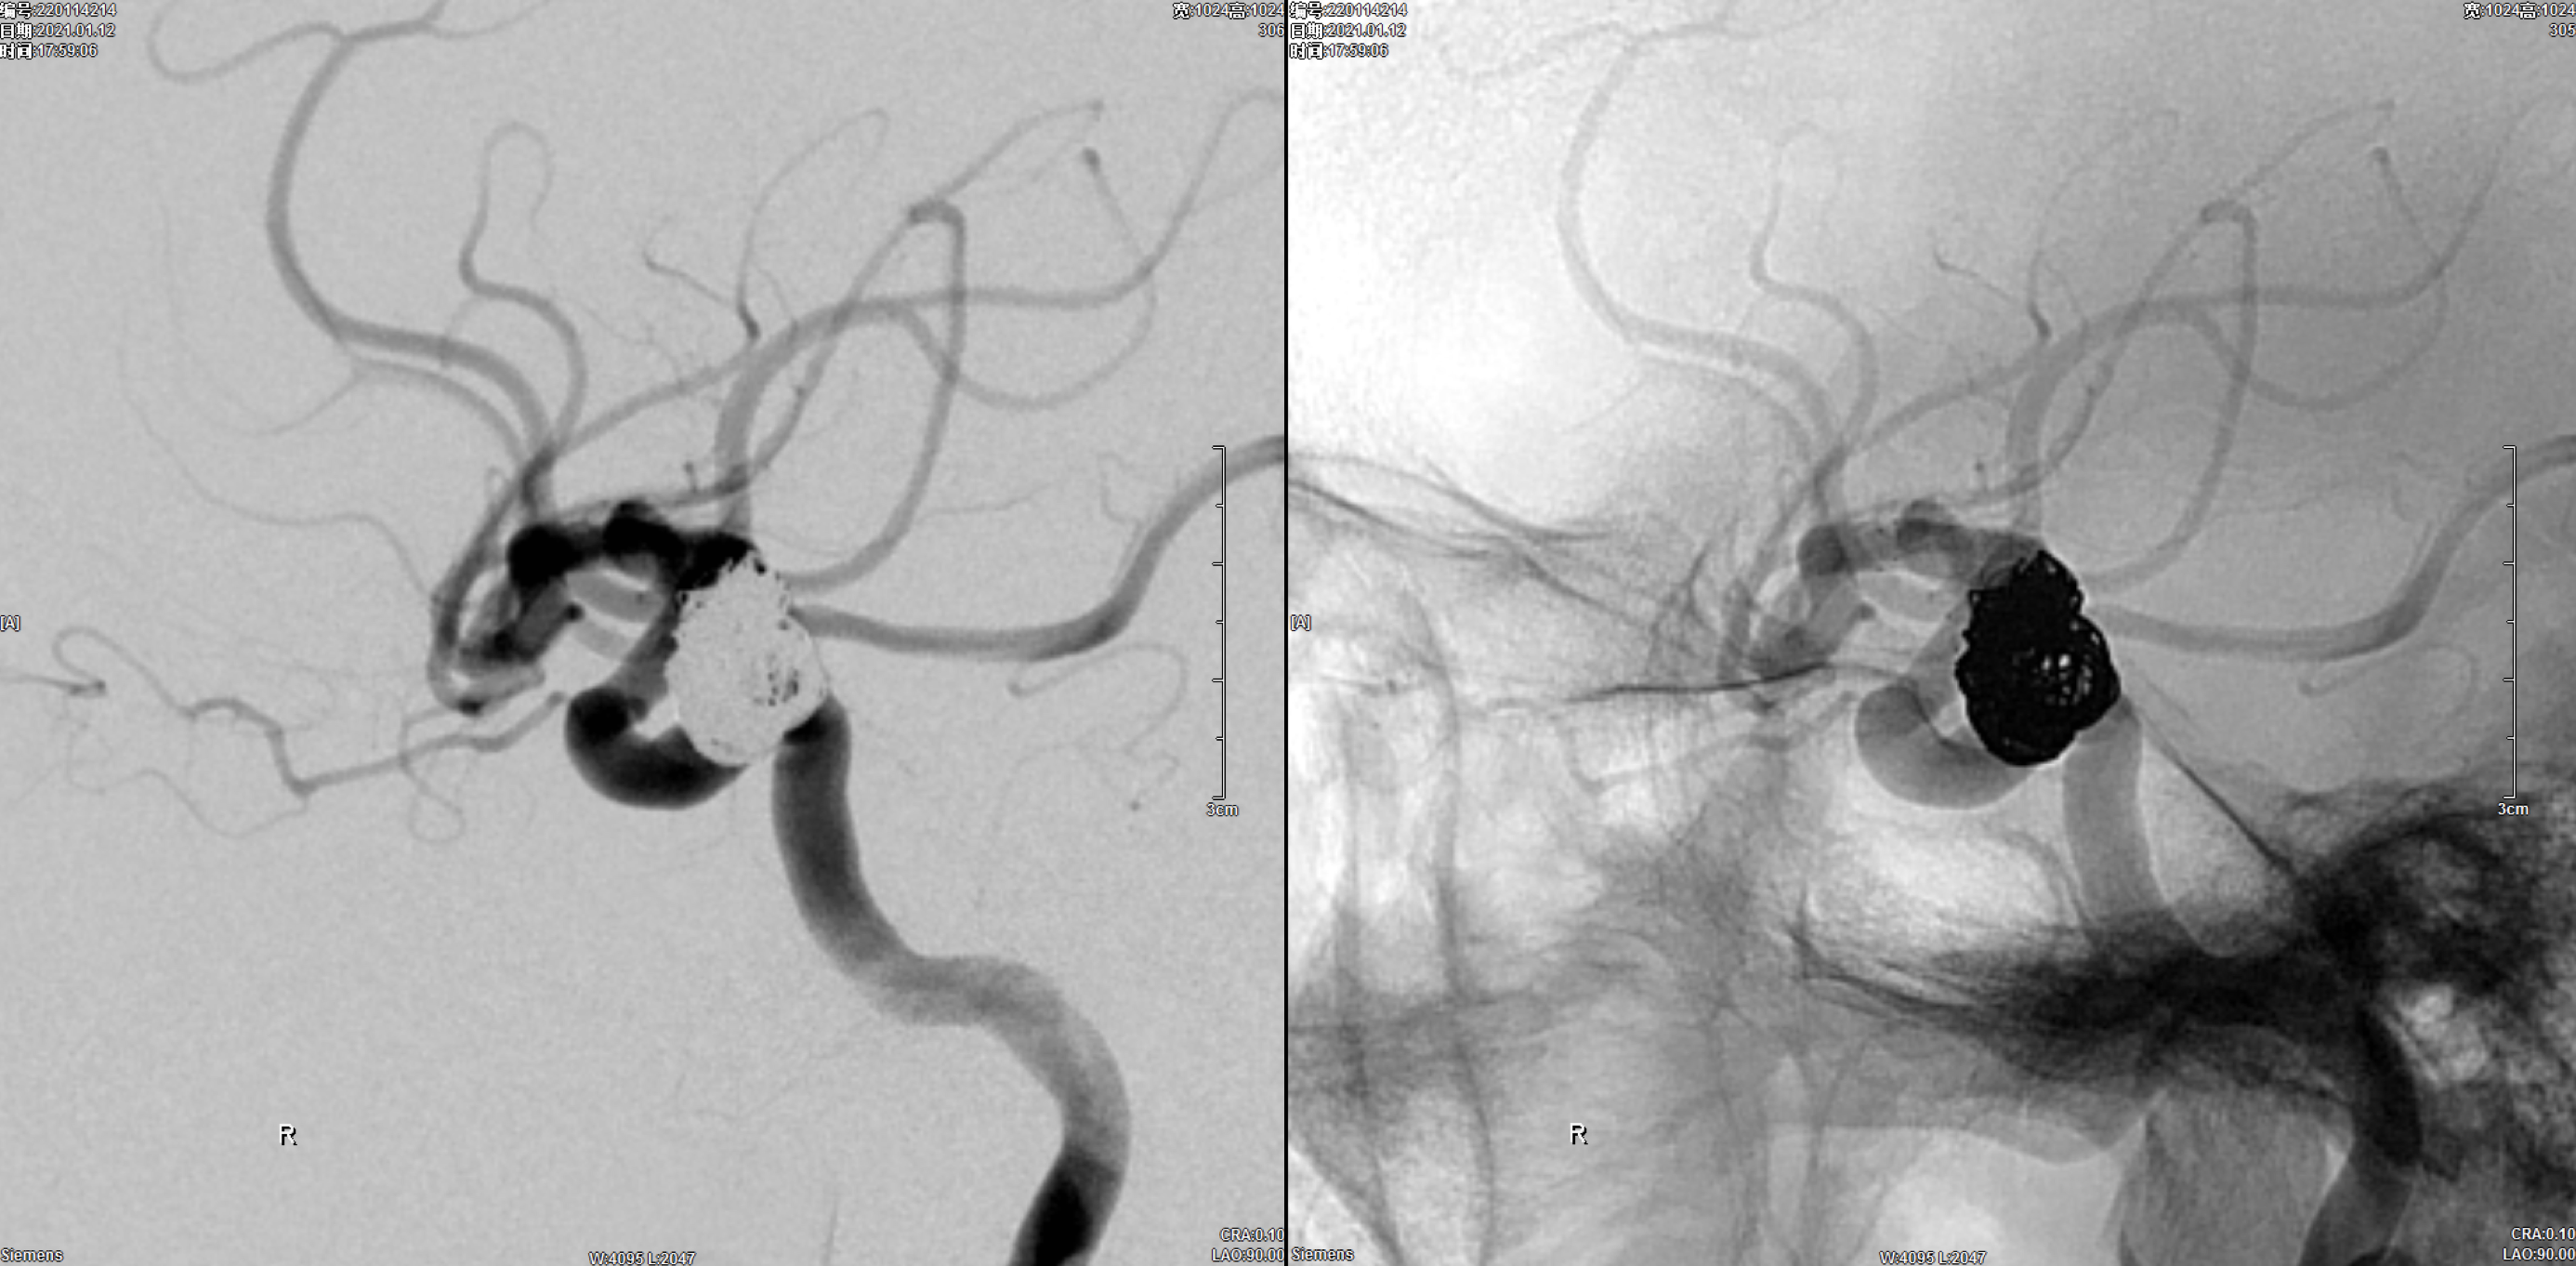

术后即刻正位造影:动脉瘤栓塞满意!

术后即刻侧位造影:动脉瘤栓塞满意!

术后三维重建:动脉瘤栓塞满意,后交通动脉保留!